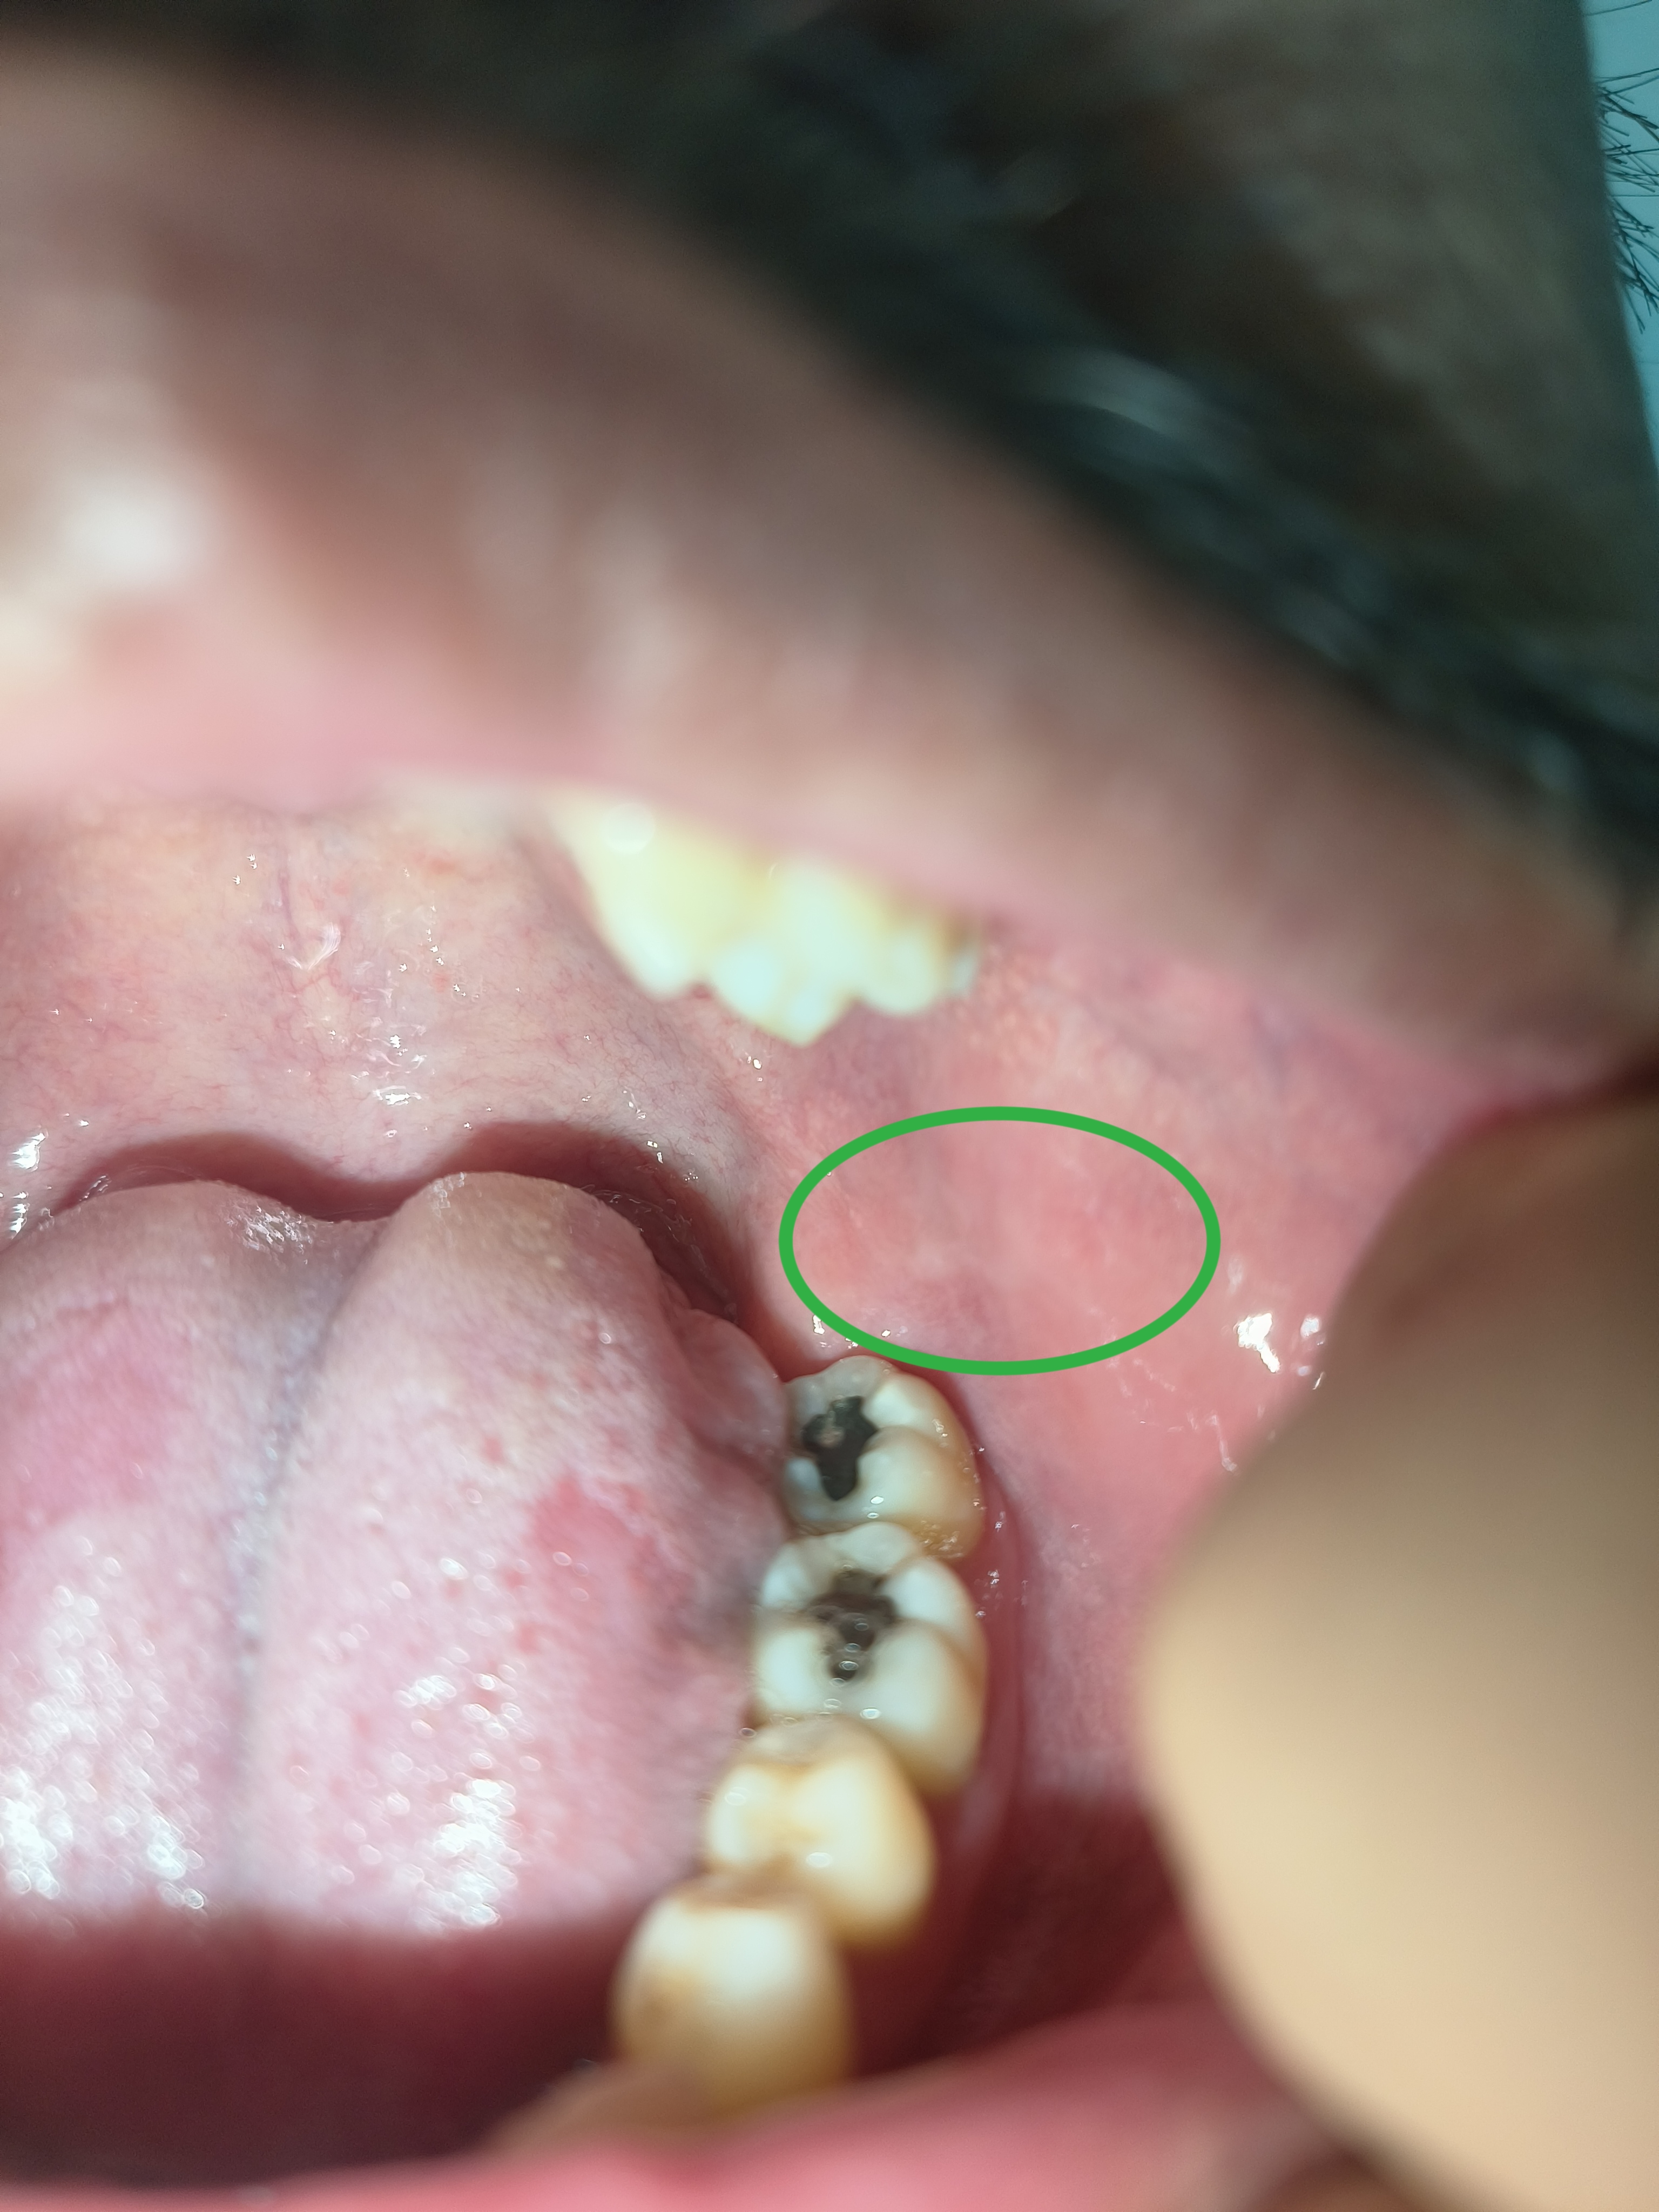

13 พฤศจิกายน 2568 14:06:03 #1 1. มีอาการเป็นแผลร้อน ที่กระพุ้งแก้มซ้ายขวา ประมาณวันที่ 23 ตุลาคม แผลเริ่มสมานตัววันที่ 26 ตุลาคม หลังจากแผลหายแล้วสังเกตุว่าบริเวณที่เคยเป็นแผลร้อนในมีลักษณะเป็นขาวๆ ตามที่ได้วงไว้ และมีอาการฝาดเฝื่อนกระพุ้งแก้ม หลังจากแผลสมานตัวแล้ว เป็นมาเกือบสามอาทิตย์ จนถึงวันนี้ครับ ไม่ทราบว่าแบบนี้ ถือว่าปกติมั้ยครับ ส่วนตัวเป็นกรดไหลย้อนขึ้นคอ บ่อย เป็นๆหายๆ ครับ 2. บริเวณด้านข้างของลิ้นเกือบๆ โคนลิ้นเห็นเป็นตุ่มแดงๆ ส่วนตัวผมดูแล้ว เหมือนจะเป็นแผลด้วยครับ ผมไม่เเน่ใจว่าเกิดจากการที่มันไปครูดใส่ฟันกรามมั้ย แต่เป็นทั้งสองข้างครับ รู้สึกไม่สบายใจ

จึงเรียนมาเพื่อปรึกษาแพทย์ครับ ขอบพระคุณครับ https://haamor.com/media/create_topic/20251113135659.jpg https://haamor.com/media/create_topic/202511131356591.jpg |

14 พฤศจิกายน 2568 12:38:49 #2 สองภาพแรก รอยแผลที่หายจากแผลร้อนใน ที่กระพุ้งแก้ม จะค่อยๆหายเป็นปรกติ เช่นนี้เอง ส่วนสองภาพหลัง แผลที่ลิ้นเป็นแผลนูนที่ข้างลิ้

สาเหตุอาจมาจากฟันผุ และคมบาดลิ้น ควรแก้ไข ห้ามปล่อยทิ้งไว้นาน จะเป็นผลเสียหายตามมามาก ควรพบทันตแพทย์ถ้าฟันที่คมบาดลิ้

แต่ถ้าไม่ใช่สาเหตุนี้ ต้องวินิจฉัยก่อนและรักษาให้

สรุป แผลที่ข้างลิ้นควรพบทันตแพทย์